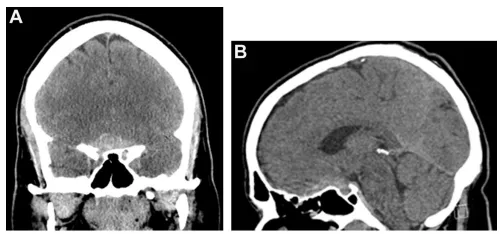

脑膜瘤是中枢神经系统肿瘤中,最具有特征性影像学表现的肿瘤。在X线和脑室造影的年代,检查结果仅起到提示作用。现在,影像学技术可以对脑膜瘤进行无创、准确地诊断,明确病灶与周围...

脑膜瘤是最常见的轴外原发性脑肿瘤,占所有颅内原发肿瘤的13%19%。脑膜瘤的生物学行为高度依赖于肿瘤大小、解剖位置、与神经血管结构的毗邻关系及组织病理学特征。其具有渐进性及隐匿性...